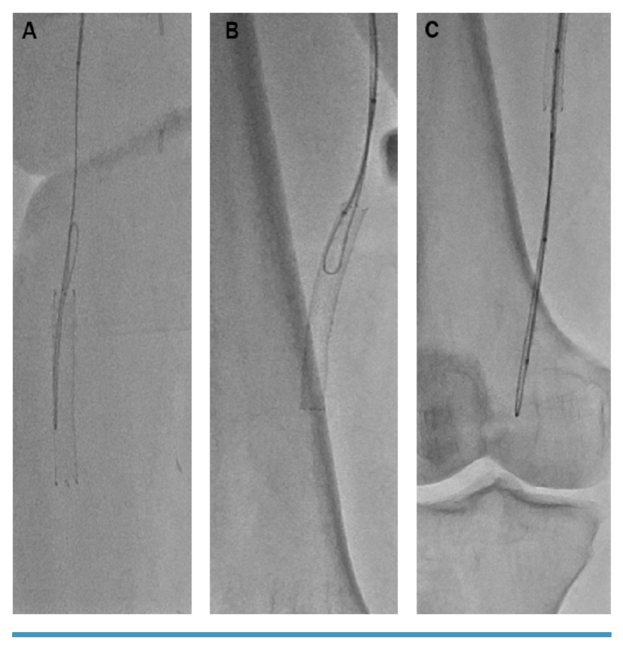

She was re-evaluated for revascularization to prevent a major amputation. The new strategy was based on antegrade and retrograde access with possible subintimal flossing with delivery of therapy from the antegrade access. The retrograde access was obtained to assist with crossing of the extensive multilevel disease. Extravascular ultrasound (EVUS)-guided left CFA and retrograde right DPA were obtained. A 7-Fr x 45-cm Destination sheath (Terumo) was inserted in the left CFA and a retrograde 2.9-Fr micropuncture pedal sheath (Cook Medical) was inserted in the right DPA. The combination of an angulated, 150-cm, .035˝ Navicross (Terumo) with 0.035” Glidewire Advantage support catheter (Terumo) crossed the proximal SFA-CTO cap intraluminally then crossed subintimally from the mid SFA to the P3 POP artery segment. Through the retrograde 2.9-Fr micropuncture pedal sheath, an .018˝ CXI support catheter (Cook Medical) and an .014˝ Fielder XT wire (Asahi Intecc) were advanced through the DPA into the anterior malleolar collateral into the PRA for rendezvous with the antegrade catheter in the ostial TPT for wire externalization. After removal of the Fielder XT wire, a V18 wire (Boston Scientific) was inserted through the retrograde .018˝ CXI support catheter and advanced in the antegrade .035˝ Navicross catheter (Figure 5 and Figure 6). We established subintimal arterial flossing with antegrade-retrograde intervention (SAFARI technique) in the TPT through the struts of the previously deployed stent extending from the distal POP to the proximal ATA with a 330-cm-long, .014˝ ViperWire. An .014˝ Eagle Eye intravascular ultrasound (IVUS) catheter (Philips) was inserted for additional evaluation and to determine the optimal treatment. IVUS revealed moderate circumferential plaque, subintimal SFA and POP crossing, and intraluminal PRA crossing with re-entry in the TPT. An Emboshield NAV6 distal embolic filter (Abbott) was placed in the distal PRA to protect the single vessel to the foot. The PRA was predilated with a 3.5- x 150-mm Ultraverse balloon (BD). The TPT was predilated with a 4.0- x 150-mm Ultraverse balloon. The POP was serially predilated with 4.0- x 150-mm, 5.0- x 150-mm, and 6.0- x 150-mm Ultraverse balloons. The SFA was serially predilated with 5.0- x 150-mm, 6- x 150-mm, and 7- x 150-mm Ultraverse balloons.